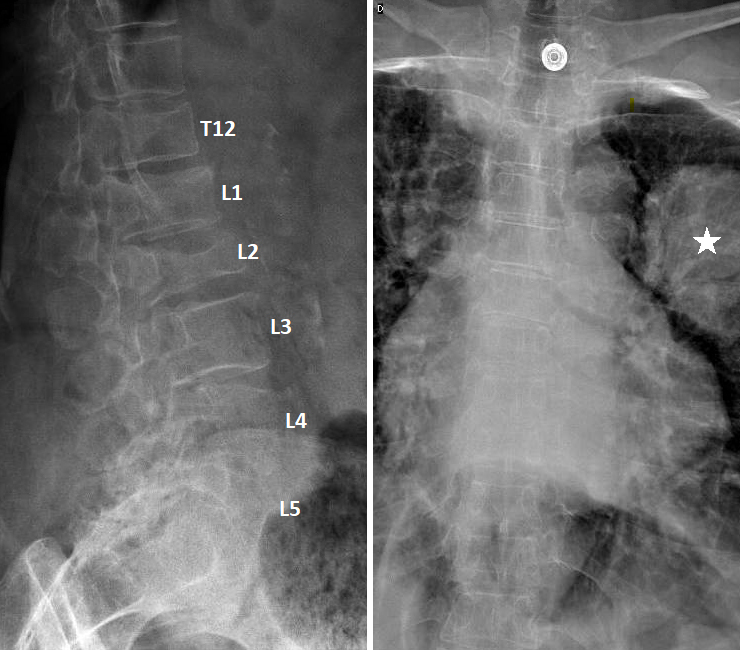

Vous faites réaliser une radiographie du rachis dorso-lombaire dont voici les clichés. Figure 1 (Salomé Abdellaoui, La Revue du Praticien)

Question 4 - Qu’identifiez-vous sur cette radiographie (une ou plusieurs réponses exactes) ?

Il existe bien une image pulmonaire suspecte mais elle est située dans le poumon gauche (légendée par une étoile).

Il s’agit d’une électrode d’électrocardiogramme.

On observe sur les radiographies une fracture vertébrale de L2, qui n'a pas de caractère évident de malignité (voir la suite du dossier), ainsi que des fractures plateaux supérieurs des vertèbres T12 et L1. Figure 2 (Salomé Abdellaoui, La Revue du Praticien)

Devant la présence d’une image pulmonaire gauche suspecte, vous craignez que la fracture vertébrale identifiée en L2 soit d’origine néoplasique.

Figure 4 (Salomé Abdellaoui, La Revue du Praticien) L’imagerie montre une fracture de L2 en hyposignal T1 avec un recul du mur postérieur, ainsi que des fractures consolidées des plateaux vertébraux supérieurs de T12 et L1. Les fractures suspectes avec recul du mur postérieur sont réputées instables et nécessitent un avis orthopédique avant d’autoriser la mobilisation. En attendant l’avis ou en cas de fracture instable, on recommande un repos au lit strict et des mobilisations avec port d’un corset rigide. Un avis oncologique est recommandé devant cette forte suspicion de néoplasie, afin d’orienter la prise en charge et de débuter le suivi par une équipe dédiée. La biopsie est indispensable pour confirmer le diagnostic de cancer, mais le traitement ne pourra (dans l’immense majorité des cas) être débuté qu’après réception des résultats histologiques.